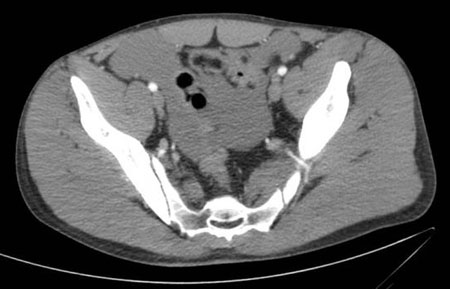

Lesão de bexiga

história de traumatismo contuso ou penetrante; associado a fraturas pélvicas; dificuldade de micção e hematúria macroscópica

Exame físico

desconforto na parte inferior do abdome

Primeira investigação

Outras investigações

- tomografia computadorizada (TC) do abdome e da pelve com contraste intravenoso e imagem tardia da pelve:

líquido livre na pelve

Mais

Lesão vascular abdominal

história de traumatismo penetrante no abdome ou pelve mais comum que de traumatismo contuso

abdome distendido, taquicardia; sinais de instabilidade hemodinâmica, hipotensão; possível perda de pulsação nos membros inferiores